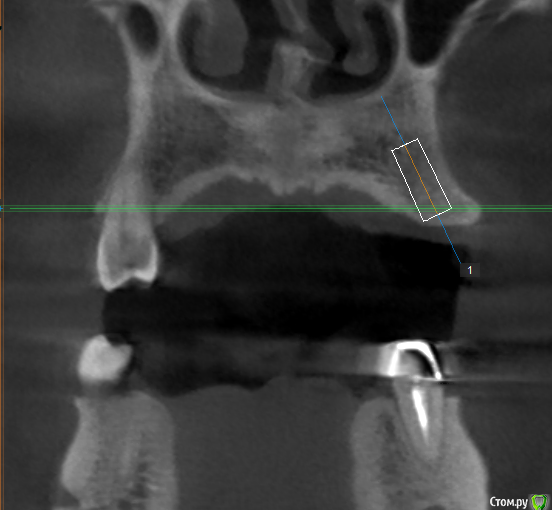

Evikrol Опубликовано 16 мая, 2018 Поделиться Опубликовано 16 мая, 2018 Я бы вот так поставил и подлиннее и на винтовую 5 Ссылка на комментарий